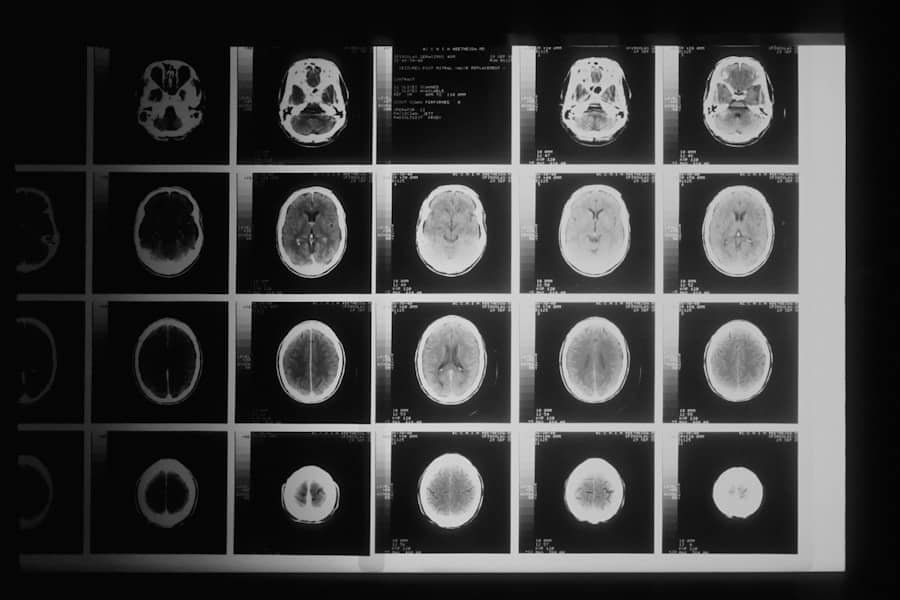

Pacijentkinja je imala hordom – retki, sporo rastući tumor koji je zahvatao vratni deo kičme i pritiskao kičmenu moždinu. Tradicionalni pristupi tumorima kičme nosili bi visok rizik od oštećenja kičmene moždine i važnih krvnih sudova i nerava. Transorbitalna procedura omogućila je izradu hirurškog puta kroz dno očne duplje bez spoljašnjih ožiljaka, čuvajući kritične strukture kao što su jugularna vena, karotidna arterija i nervi za gutanje i govor.

Lekari iz više specijalnosti, uključujući neurohirurgiju, plastičnu hirurgiju lica i radioonkologiju, sproveli su složene operacije kako bi uklonili dva zasebna tumora, koristeći savremene endoskopske instrumente za preciznu navigaciju i minimalan rizik. Nakon uklanjanja tumora, pacijentkinja je dobila fuziju pršljenova u vratu i protonsku radioterapiju za eliminaciju preostalih malignih ćelija.